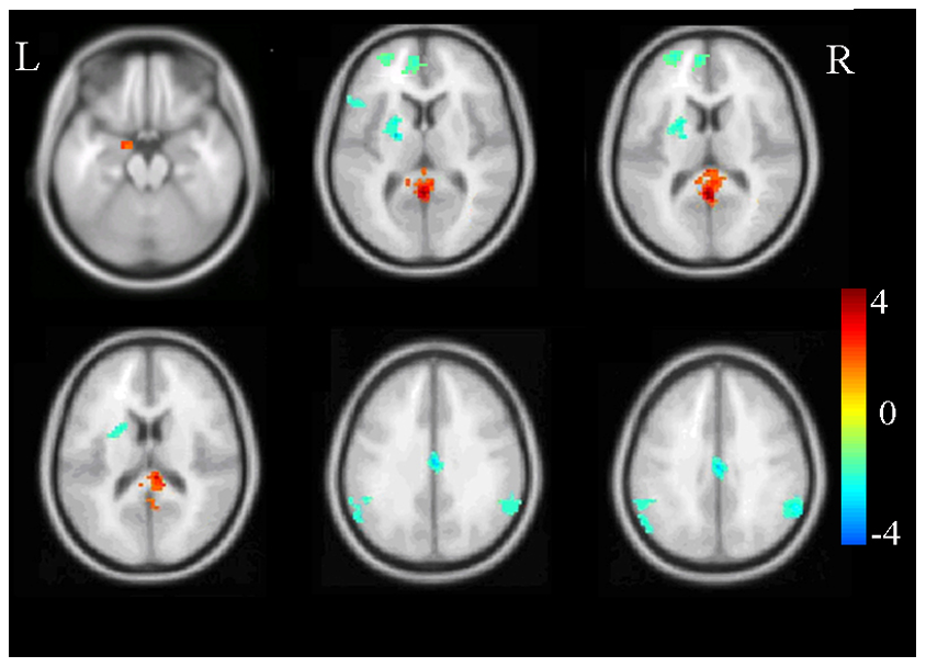

Then there is functional MRI (fMRI). This method examines blood flow in different areas of the brain as a measure of their dynamic function, mostly in response to a task or event, such as thinking about trauma or viewing of a trauma-related image. I use fMRI in my research to look at the brain circuitry involved in how people can be instructed to learn fear and safety. Positron emission tomography, or PET, and single photon emission CT, or SPECT, are also used in looking at brain function.

Although we do not use brain scans to diagnose PTSD in the clinic, we use them to understand what happens in the PTSD brain. There is abundant evidence for changes in the structure and function of different areas of brain involved in fear response and anxiety, regulation of emotions, cognitive processing and memory. For example, there is consistent evidence for reduced volume in the brain region called the hippocampus, which is involved in memory and context processing. This leads to difficulties differentiating cues that resemble trauma, such as the slamming of a door, from the trauma cue itself, such as a gunshot.

Abnormalities of the hippocampus also lead to impairments of differentiating a safe context from the context in which trauma happened. For example, this could be a fear response to road kill in Ann Arbor, Michigan, which may resemble an improvised explosive device (IED) in Iraq. We also know from fMRI research, the part of the brain called the amygdala, which is involved in fear response, shows larger activation in response to viewing or memory of trauma reminders, or viewing of negative facial affect. These findings are valid in studies averaging data across brain scans of dozens of people. They are not useful in a one-person diagnosis.

To summarize, brain imaging has been a very useful tool in understanding the aberrations in structure and function of a PTSD brain, but it does not diagnose the condition.